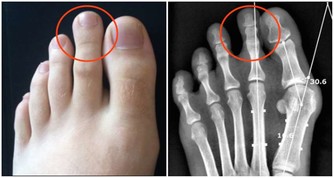

關節僵硬:它們最怕5個字

關節是骨骼之間的連接點,一旦關節出了問題,人的行動力就會受限,久之人就垮了。

1、怕老:隨著年齡的增長,人體軟骨營養缺乏,骨骼中的無機物增多,骨骼彈力與韌性減低,易導致關節軟骨和骨退行性病變。

2、怕胖:體重增加,下肢關節承重的壓力也會增加,引起體位、步態變化,改變關節的生物力學,發生膝內翻或膝外翻,也就是常說的“O”形腿或“X”形腿。

3、怕傷:在運動、出行的過程中,如果出現急性外傷,一定要及時去醫院治療,以免留下後遺症。

不及時治療或充分休息,容易留下病根,比如“習慣性崴腳”。